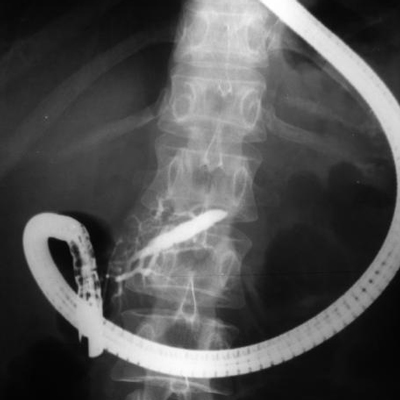

ERCP

Kronik pankreatitisin nedeni eğer, safra veya pankreas kanalının daralması veya tıkanması veya psödokist olarak tanımlanması durumunda, Endoskopik retrograd kolanjiyopankreatografi veya ERCP ile ileri terapötik endoskopi ile tedavi edilebilir. Bu işlemler kanalın genişletilmesi, kanalın açık kalması için bir stentin (içi boş bir tüp) yerleştirilmesi, bir safra kanalı darlığını tedavi etmek için bir sfinkterotomi ve stent yerleştirilmesi, kistin boşaltılması veya çıkarılmasını içerir. Tekrarlayan bir atak için önleyici tedbirler de hastalar için tavsiye edilir. Sigara ve alkollü içeceklerden ve fazla yağlı bir diyet yemekten kaçınmayı içerir.